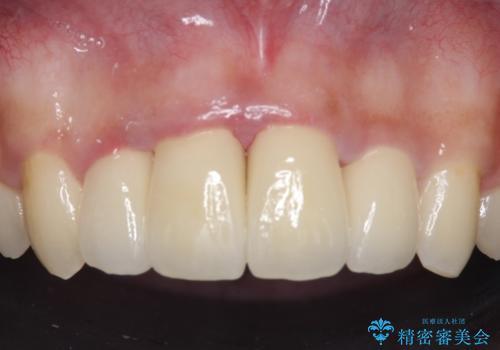

- 上顎前歯の歯並びが気になるが仕事が忙しく矯正治療は難しいため、セラミック矯正で綺麗にしたいといらっしゃった方の症例です。

左右の1番目の歯は傾きが大きいため、セラミッククラウンにするにあたり神経治療を行うことを御了承頂いた上で、前歯4本をオールセラミッククラウン(スペシャル)により補綴しました。

前歯の補綴ではオールセラミッククラウンを希望される患者様が多いですが、オールセラミッククラウンの中でも、エコノミー、スタンダード、スペシャル、エクセレントとランクがあります。

その中でも特に審美性が高いのがスペシャル、エクセレントです。スペシャル、エクセレントは口腔内写真をもとに熟練の技工士が、患者様の口腔内に合わせたオーダーメイドのクラウンを製作致します。